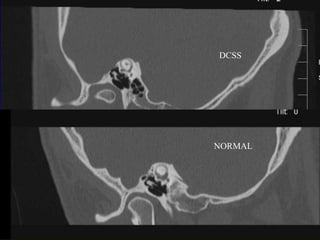

DCSSNORMAL

Discusión El TCMC no tiene falsos negativosSi está el hueso se excluye la enfermedadPudieran existir falsos positivosDados por efecto de volumen parcialLa cápsula ótica pudiera ser menor de 0,5mm y formaría la barrera protectoraUn voxel ocupado parcialmente (1/5) da una atenuación mayor Dehiscencia sin síntomas por dura gruesa